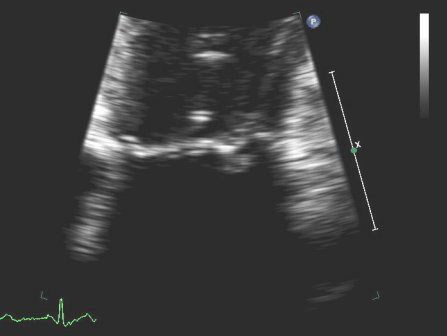

[Figure caption and citation for the preceding image starts]: Apical 3-chamber view of hypertrophic cardiomyopathy with systolic anterior motionFrom the collection of Samir Kapadia and Mehdi H. Shishehbor [Citation ends].

[Figure caption and citation for the preceding image starts]: Apical 4-chamber view of flail posterior mitral leafletFrom the collection of Samir Kapadia and Mehdi H. Shishehbor [Citation ends].

[Figure caption and citation for the preceding image starts]: Parasternal long-axis view showing posterior mitral leaflet prolapseFrom the collection of Samir Kapadia and Mehdi H. Shishehbor [Citation ends].